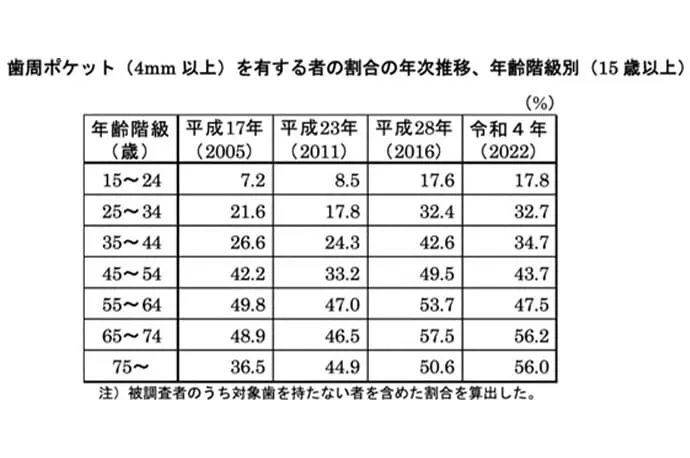

2018年の8020推進財団の調査では、歯を失う原因として最も多いのが歯周病であることが明らかになりました。また、2022年の歯科疾患実態調査によると、25歳以上の約30%が歯周病に罹患しており、45歳以上では40%以上、65歳以上では50%以上にのぼると報告されています。

令和4年歯科疾患実態調査の結果(概要)(厚生労働省)より引用

令和4年歯科疾患実態調査の結果(概要)(厚生労働省)より引用

令和4年歯科疾患実態調査の結果(概要)(厚生労働省)より引用

歯は顎の骨によって支えられています。歯と歯ぐきの間には「歯周ポケット」と呼ばれるすき間があり、健康な状態では深さは3mm以下です。

しかし、歯ぐきに炎症が起きたり、歯を支える骨が破壊されている場合には、歯周ポケットが4mm以上に深くなります。まずはこの歯周ポケットの状態を詳しく検査します。